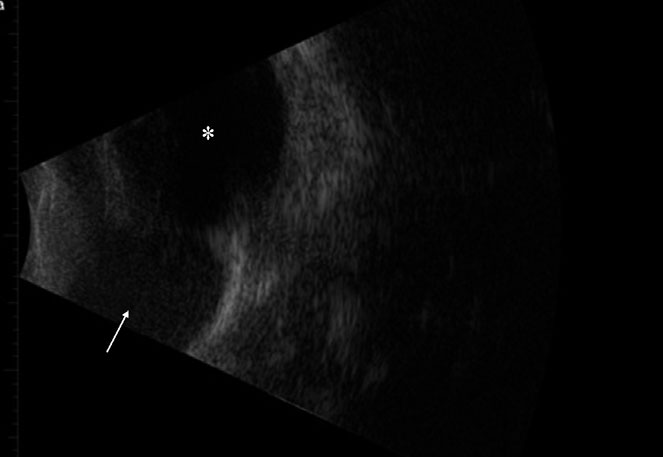

The patient was sedated with dexmedetomidine (375 mcg/m² IV; Dexdomitor, Zoetis, Florham Park, NJ, USA) and butorphanol (0.4 mg/kg IV; Torbugesic, Fort Dodge, Fort Dodge, IA, USA). After sedation, ocular ultrasound imaging (10 mHz UBM probe; Aviso, Quantell Medical, Bozeman, MT, USA) was obtained and showed an anechoic to mildly hypo-echoic, well-demarcated, homogenous, soft tissue mass at the base of the third eyelid with no orbital extension (Fig. 2). Based on the ultrasound and readily accessible location for tissue sampling, biopsies of the mass were pursued. After routine surgical preparation, local anesthetic was injected subconjunctivally on the palpebral surface of the third eyelid overlying the mass with 2% injectable lidocaine (0.15 mL subconjunctival; MWI, Boise, ID, USA). Several 4-mm punch biopsies (disposable biopsy punch; Miltex, York, PA, USA) were obtained from the palpebral surface of the third eyelid in the body of the firm, intrapalpebral mass and submitted for histopathologic examination. The conjunctival defect was closed with simple interrupted 6-0 vicryl (Ethicon; Johnson and Johnson, New Brunswick, NJ, USA) sutures. The patient’s dexmedetomidine sedation was then reversed using atipamezole (375mcg/m² IM; Antisedan, Zoetis, Florham Park, NJ, USA). The patient recovered routinely and was discharged with topical diclofenac (1 drop Q12 h OD; Nexus Pharmaceuticals, Vernon Hills, IL, USA) and topical Optimmune as previously prescribed.